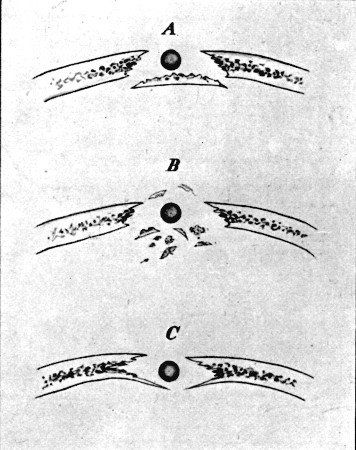

Nature of wounds—Explosive wounds—Types of fracture of shafts of long

bones—Stellate, wedge, notch, oblique, transverse,

perforating—Fractures by old types of bullet—Lesions of the short and

flat bones—Special character of the symptoms in gunshot fracture, and

of the course of healing—Prognosis—Treatment—Special fractures—Upper

50. Types of Gunshot Fracture161

52. Oblique Perforation of Femur, Separation of Fragment at Exit Aperture in Bone169